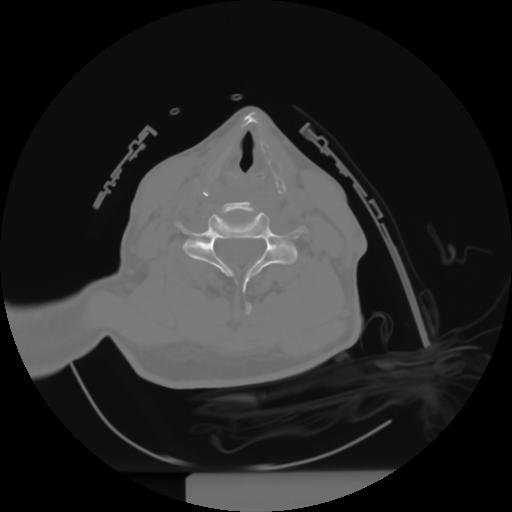

10 P.BLANDAS,,Axial,2.0,P.BLANDAS,,